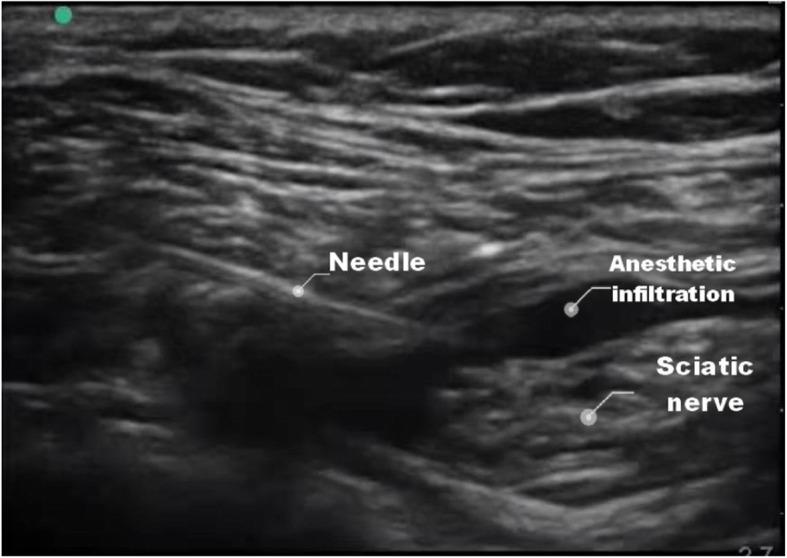

Ultrasound-guided single popliteal sciatic nerve block is an effective postoperative analgesia strategy for calcaneal fracture: a randomized clinical trial.

A total of 120 patients scheduled for unilateral open reduction and internal fixation of calcaneal fracture were enrolled in this prospective randomized study. Patients in group B received ultrasound-guided single popliteal sciatic nerve block after operation, but Patients in group A did not. All patients received patient-controlled intravenous analgesia (PCIA) after operation. The time to initiation of PCIA, the time of first pressing the analgesia pump, duration of analgesia pump use and the total number of times the patient pressed the analgesia pump were recorded. The time of rescue analgesia and the adverse reactions were recorded. Pain magnitude of the patients immediately after discharge from operating room (T1), and at 4th (T2), 8th (T3), 12th (T4), 16th (T5), 24th (T6) and 48th (T7) h after the operation were assessed with visual analog scale (VAS). In addition, patient, surgeon and nurse satisfaction were recorded.